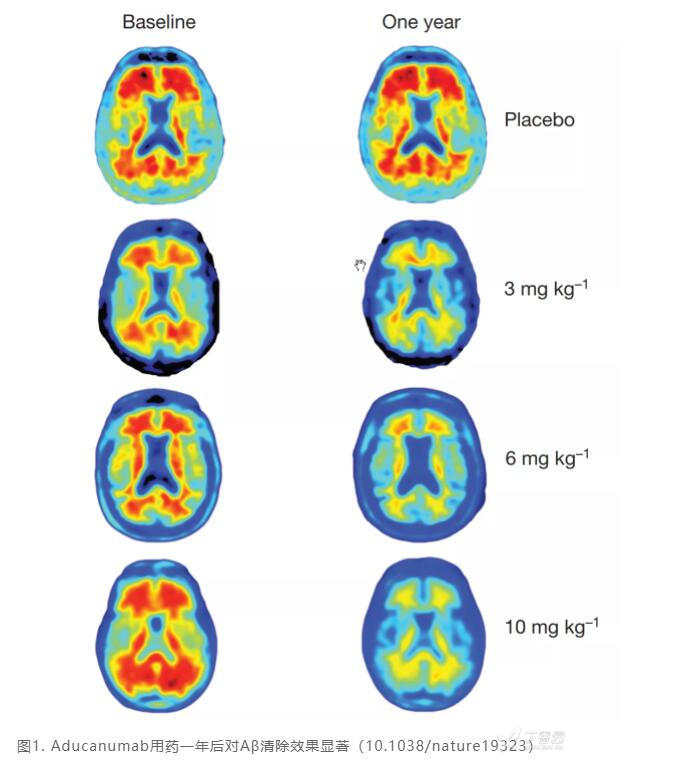

2016年也有 Nature 文献通过 PET 的方法检测 Aducanumab 对 Aβ 的强力清除能力;